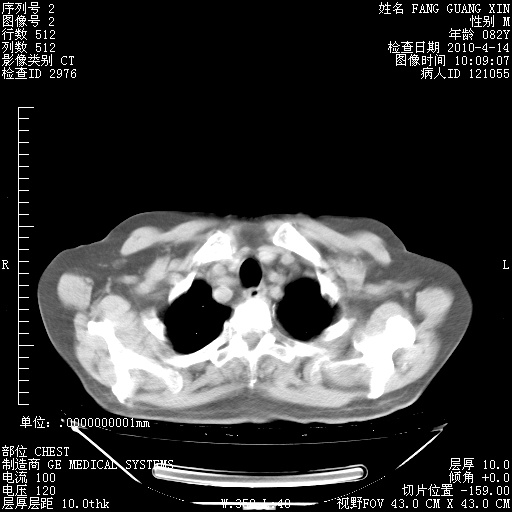

4月14日肺部CT

楼主| 发表于 2010-4-28 16:51 | 显示全部楼层

楼主| 发表于 2010-4-28 16:53 | 显示全部楼层

肺部CT平扫未见异常。